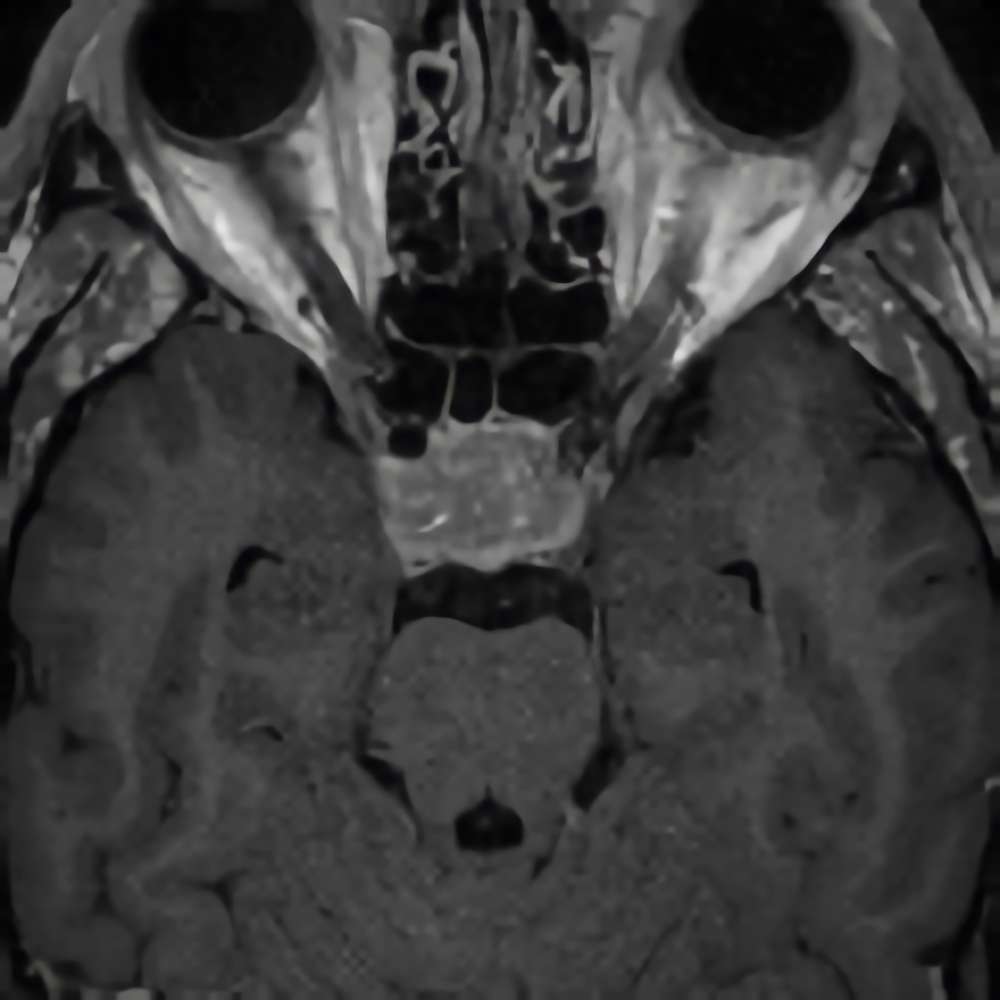

断層撮影

手術前1

手術前2